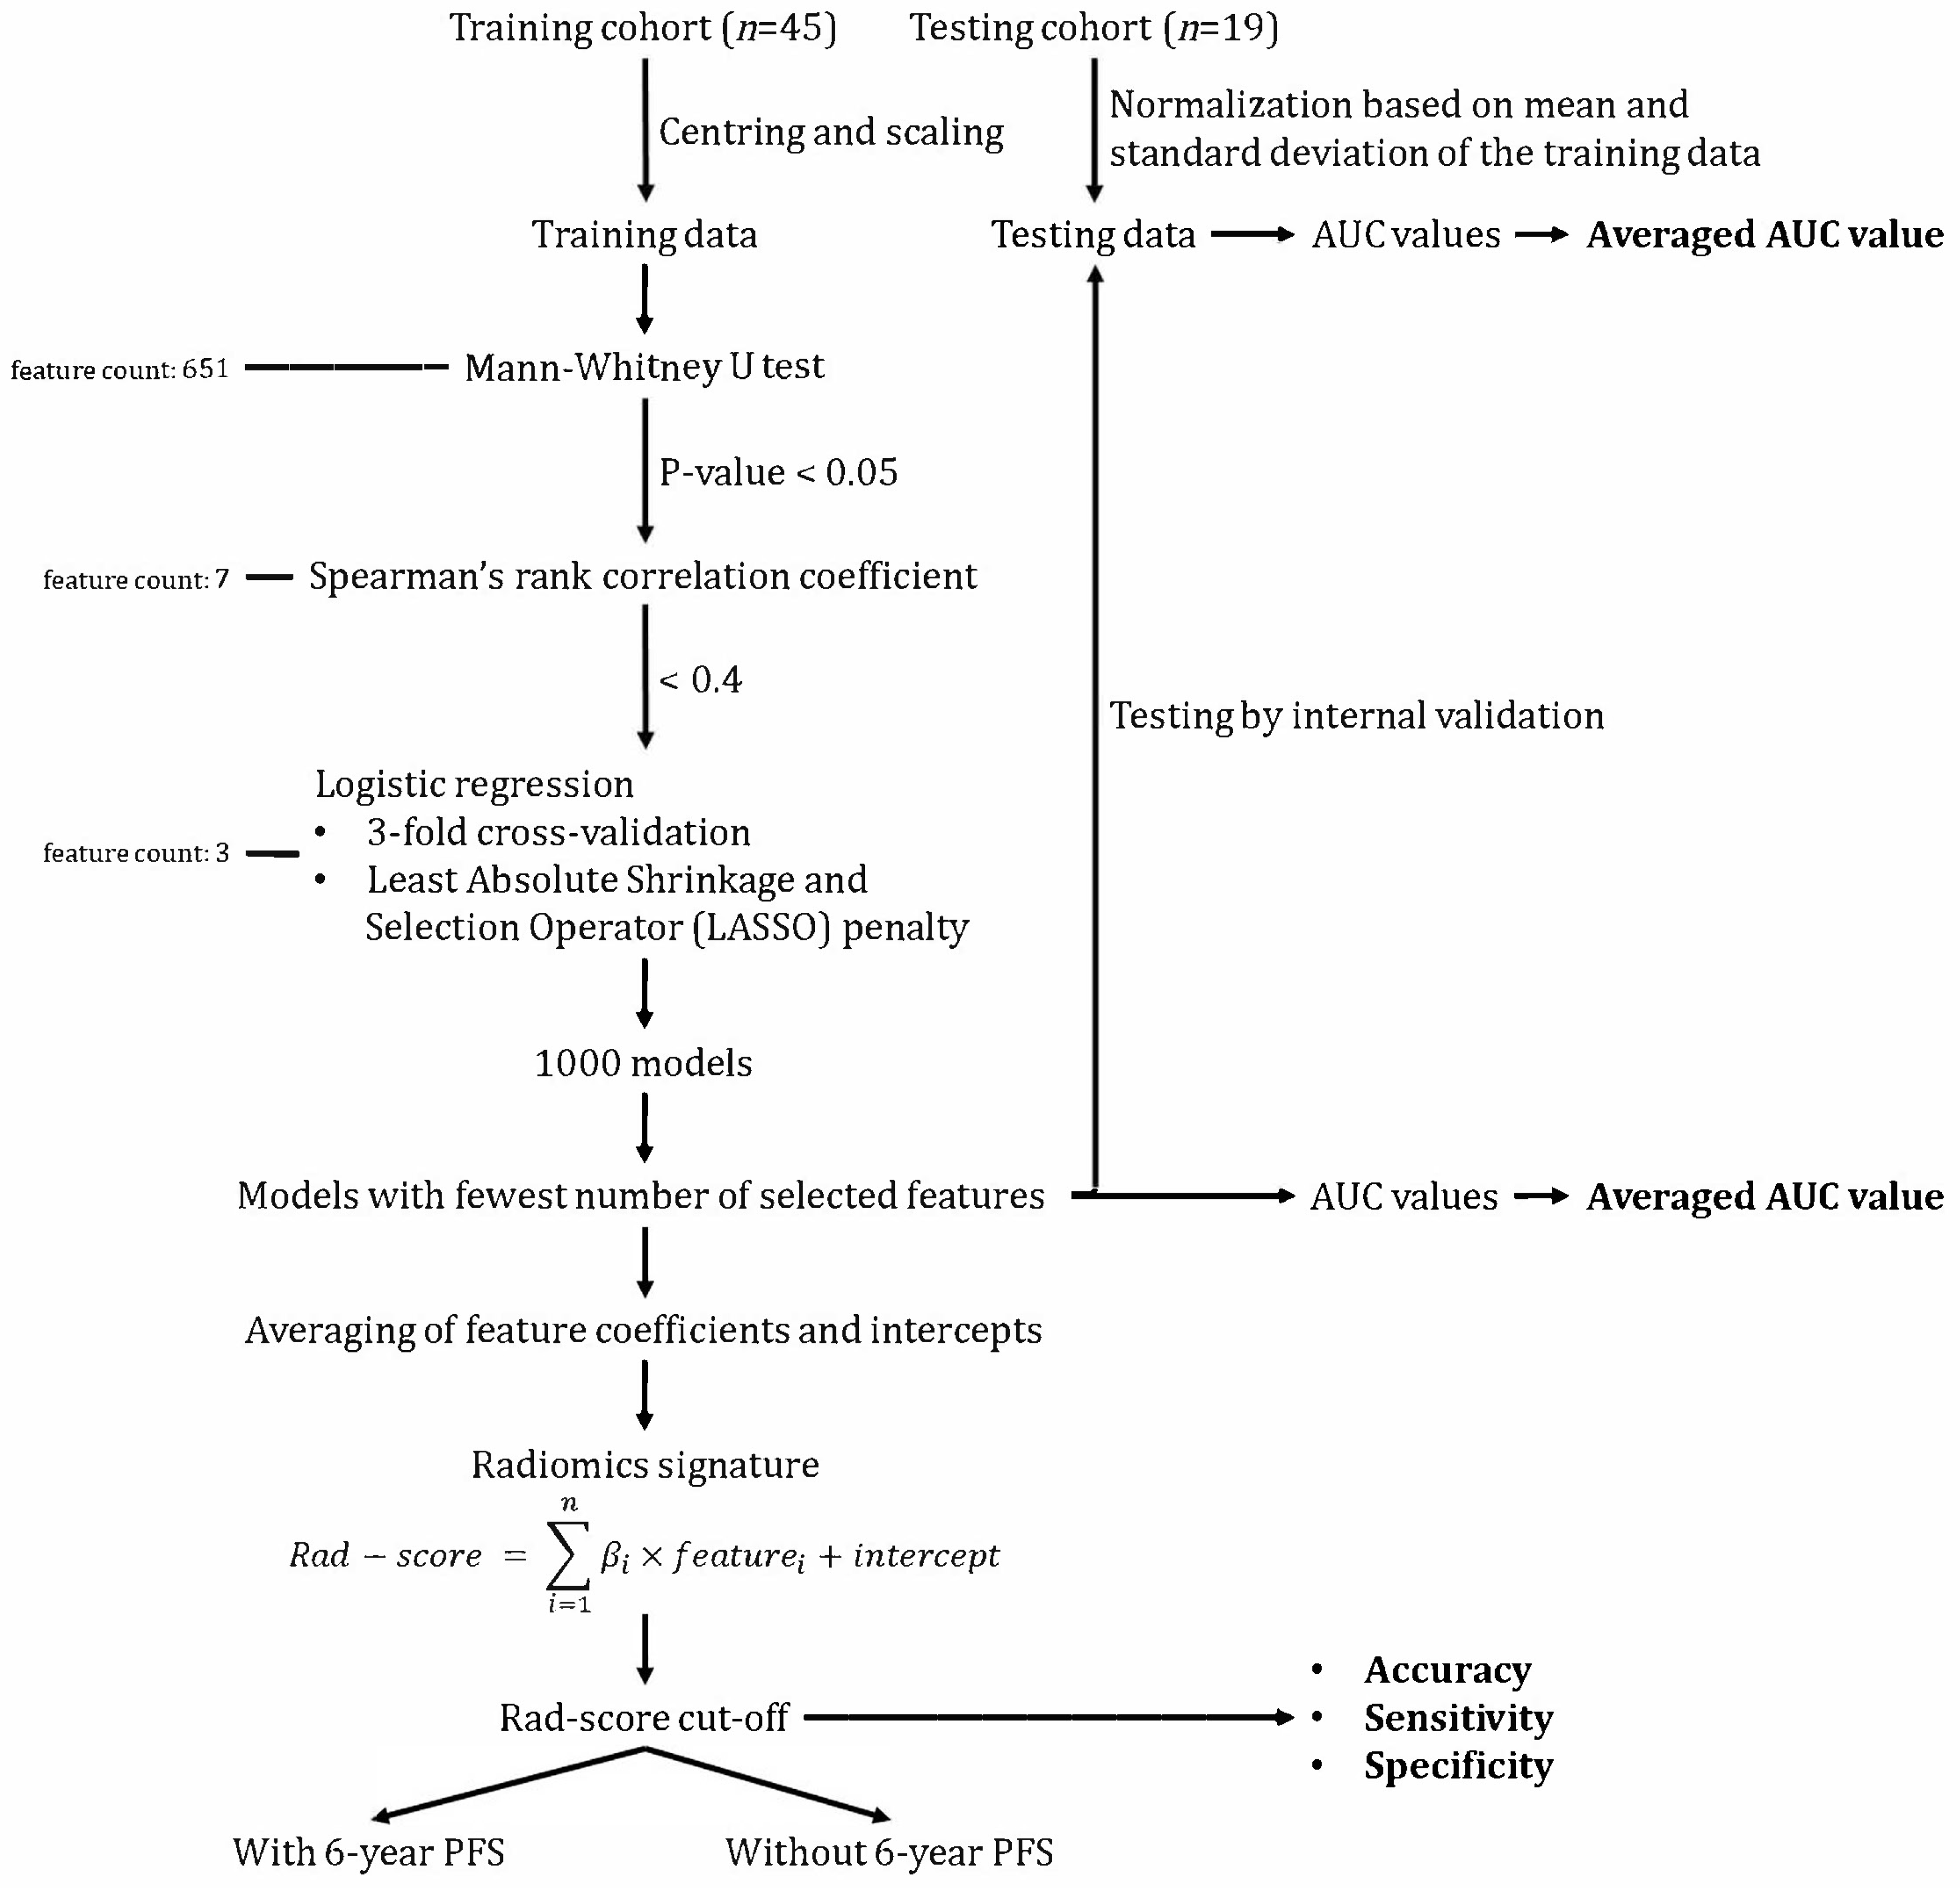

2.4.4. Feature Selection

2.4.5. Model Development

2.4.6. Statistical Analysis